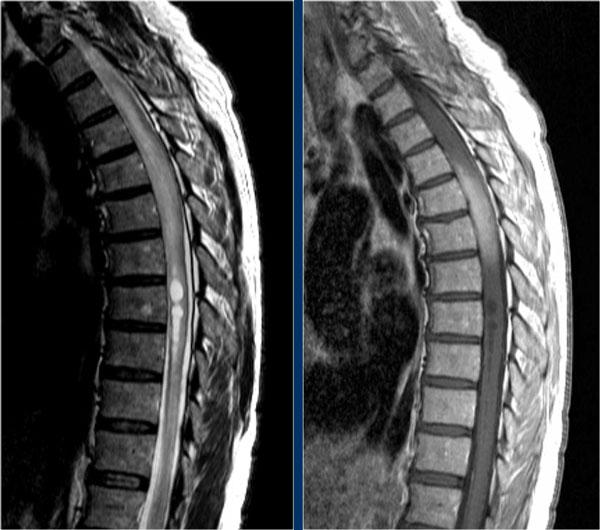

Đây là hình ảnh của một trường hợp TM điển hình.

Có tăng tín hiệu đa đoạn trên STIR và chuỗi xung T2W kèm theo phù nề nhẹ.

Phần lớn tủy sống trên đường kính ngang bị tổn thương.

Không có ngấm thuốc tương phản từ, đây thường là đặc điểm thường gặp trong TM.

Đôi khi có thể thấy ngấm thuốc dạng vá không đều.

Khi có ngấm thuốc tương phản từ, việc phân biệt TM với u tế bào hình sao (astrocytoma) có thể rất khó khăn.

Bên trái là hình ảnh của bệnh nhân nam 60 tuổi mắc u tế bào hình sao.

Bệnh nhân nhập viện với đau vùng ngực và rối loạn cảm giác chi dưới trái, tiếp theo là liệt nửa người trái.

Có tăng tín hiệu đa đoạn trên chuỗi xung T2W kèm phù nề nhẹ, tương tự như hình ảnh đã thấy trong các trường hợp TM.

Trên CE-T1W có vùng ngấm thuốc tương phản từ.

Vùng ngấm thuốc có hình thái nghiêng về u hơn, nhưng việc phân biệt vẫn còn khó khăn.